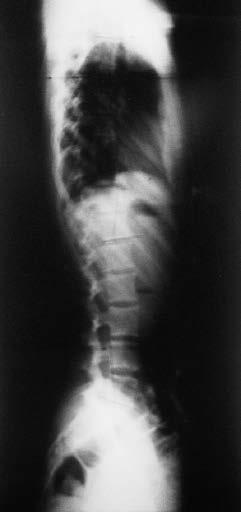

215 Abbildung 149: Verlauf einer juvenilen idiopathischen Skoliose (early onset scoliosis) mit einem Krümmungswinkel von mehr als 30 Grad im Alter von sechs Jahren. Es zeigte sich unter kontinuierlicher Korsettversorgung von ca. 16 Stunden täglich mit einem CAD-Chêneau-Korsett eine kontinuierliche Krümmungsreduktion. Mit weit weniger als 20 Grad trat die Patientin in den Pubertätsschub ein und benötigte daher in der Hauptwachstumsphase nur noch eine Tragezeit von zwölf Stunden pro Tag. LESEPROBE